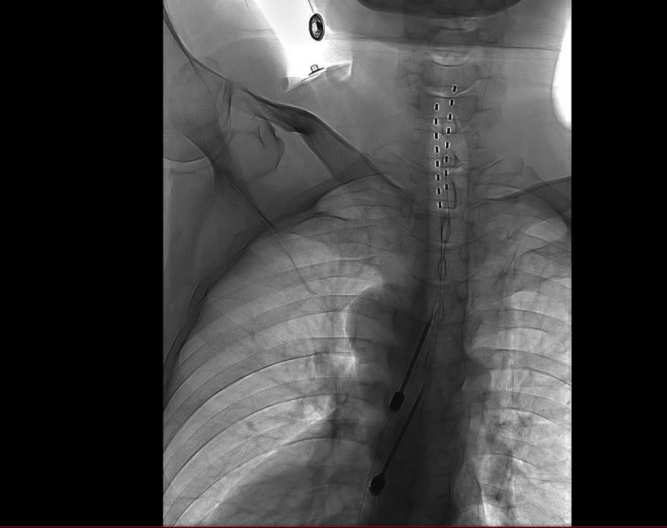

手術(shù)通過微創(chuàng)硬膜外腔穿刺技術(shù),于DSA(數(shù)字血管剪影造影)引導(dǎo)下將極細(xì)的電刺激電極與植入式脈沖發(fā)生器共同植入體內(nèi)。

手術(shù)歷經(jīng)3小時,病人恢復(fù)良好。術(shù)后1周內(nèi),團(tuán)隊根據(jù)患者疼痛緩解及感覺區(qū)覆蓋情況,對植入電極的刺激參數(shù)進(jìn)行多次動態(tài)調(diào)控,目前廖先生疼痛明顯減輕,預(yù)計可于近期順利出院。